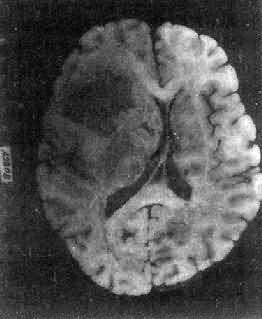

图16-24 多形性胶质母细胞瘤 发生于儿童、青少年的毛发细胞型星形胶质细胞瘤,生长极为缓慢。有报道称患者在不完全切除肿瘤后有带瘤存活达40年者。该瘤常位于小脑、第四脑室底部、第三脑室、丘脑和视神经。其形态特点是由双极性的肿瘤细胞两端发出纤细的毛发状突起。即使有毛细血管增生,本瘤的预后仍相对较好。 应该指出,同一肿瘤的不同区域,瘤细胞可有不同的形态特征,且分化程度也不尽相同,因此肿瘤的分型仅具有相对的意义。 星形胶质细胞瘤的细胞骨架含有胶质纤维酸性蛋白(GFAP),免疫组织化学染色呈阳性反应,是该肿瘤的特异标志。 2.少突胶质细胞瘤(oligodendroglioma) 约占颅内胶质瘤的5%,主要见于30~40岁的成人,男女发病的机会相等。本瘤绝大部分位于大脑半球皮质的浅层,尤以左额叶为多见。 肉眼观,肿瘤呈灰红色边界清楚的球形肿块,位于白质和邻近的皮质,并可累及软脑膜。囊性变、出血和钙化颇为常见,其中钙化灶对X线诊断有一定帮助。 镜下,瘤细胞大小均匀,形态单一,弥漫排列,胞核居中着色深,胞浆空,环绕胞核形成空晕。间质富有血管,有不同程度的内皮细胞增生。约有20%病例可出现瘤细胞钙化,其范围大小不一,其中7%为镜下钙化,有时钙化灶较大,可在X线片上显示出来。如肿瘤组织中混有星形胶质细胞瘤成分达到50%,则称混合性少突星形胶质细胞瘤。 本瘤生长缓慢,病程可长达10~30年,临床表现多为癫痫和局部性瘫痪。少数生长迅速,酷似多形性胶质母细胞瘤,预后不佳。 3.室管膜(细胞)瘤(ependymoma)起源于室管膜细胞,患者多为儿童和青少年。本瘤占颅内胶质瘤的5%~6%,多见于第四脑室,其次为侧脑室、第三脑室和导水管。脊髓病变多发生于腰胝及马尾部。 肉眼观,颅内室管膜瘤呈膨胀性生长,边界清楚,呈球形、分叶状或乳头状,肿瘤多在脑室内生长。切面灰白色,呈均匀或颗粒状,可发生灶性出血甚至坏死或囊性变,有时也可发现点状钙化。 镜下,瘤细胞大小形态一致,呈梭形或胡萝卜形,胞核圆或椭圆,染色质呈细颗粒状,核膜清楚,有核仁。瘤细胞胞浆丰富,突起明显。瘤细胞的排列有二种特征,一是环绕空腔排列成腺管状,形态上与室管膜腔相似,称为菊形团形成,另一是环绕血管形成假菊形团结构,瘤细胞有细长的胞浆突起与血管壁相连(图16-25)。细胞中有神经胶质纤维,以PTAH染色在个别细胞的腔面或胞核旁可见纤毛体,后者与纤毛运动有关,是室管膜细胞的特征性结构。此外,有时还可形成乳头状结构。发生在脊髓圆锥和终丝的肿瘤,乳头状结构轴心中的结缔组织往往富含粘液。